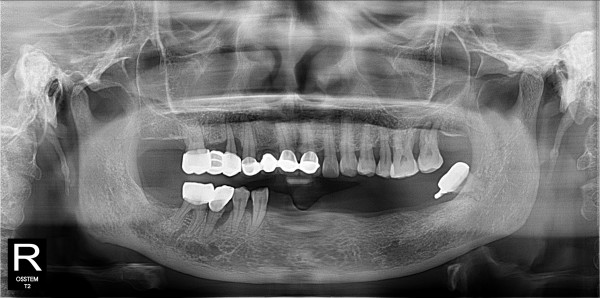

네비게이션 임플란트 최고관리자 0건 23-11-07 18:40 본문 하악 틀니에서 네이게이션 임플란트 목록 다음글네비게이션 임플란트 23.11.07 댓글목록 0 댓글목록 등록된 댓글이 없습니다.